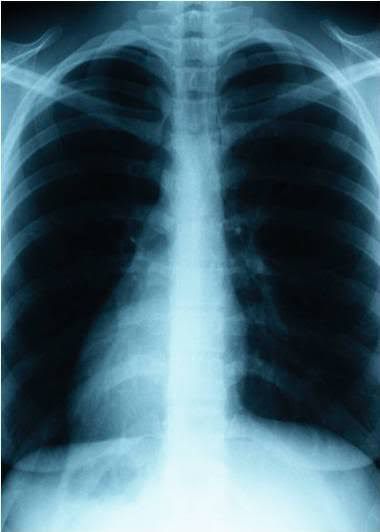

A chest infection is an infection of the lungs or airways. The main types of chest infection are bronchitis and pneumonia. Most bronchitis cases are caused by viruses, whereas most pneumonia cases are due to bacteria. These infections are usually spread when an infected person coughs or sneezes. This launches tiny droplets of fluid containing the virus or bacteria into the air, where they can be breathed in by others. The infections can also be spread to others if you cough or sneeze onto your hand, an object or a surface, and someone else shakes your hand or touches those surfaces before touching their mouth or nose. Certain groups of people have a higher risk of developing serious chest infections, such as: babies and very young children children with developmental problems people who are very overweight elderly people pregnant women people who smoke people with long-term health conditions, such as asthma, heart disease, diabetes, kidney disease, cystic fibrosis or chronic obstructive pulmonary disease (COPD) people with a weakened immune system – this could be due to a recent illness, a transplant, high-dose steroids, chemotherapy or a health condition, such as an undiagnosed HIV infection